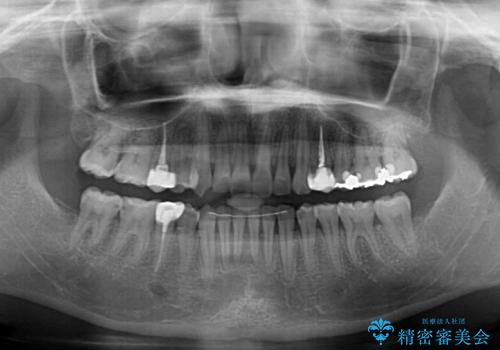

インビザラインでの矯正治療を希望されていましたが、奥歯の咬み合わせがインビザライン単独では改善困難と判断されたので、補助装置を併用することとしました。

まずは裏側の装置やワイヤー矯正を用いて歯列幅の狭い上顎を側方に拡大しつつ全体を後方に移動させ、その後インビザラインにて歯列を整えることとしました。

奥歯の咬み合わせの改善は、インビザライン単独では達成しきれないことがあるため、ワイヤー矯正などの補助装置を併用する場合があります。

インビザライン単独の場合と比べ、治療結果は大きく異なります。